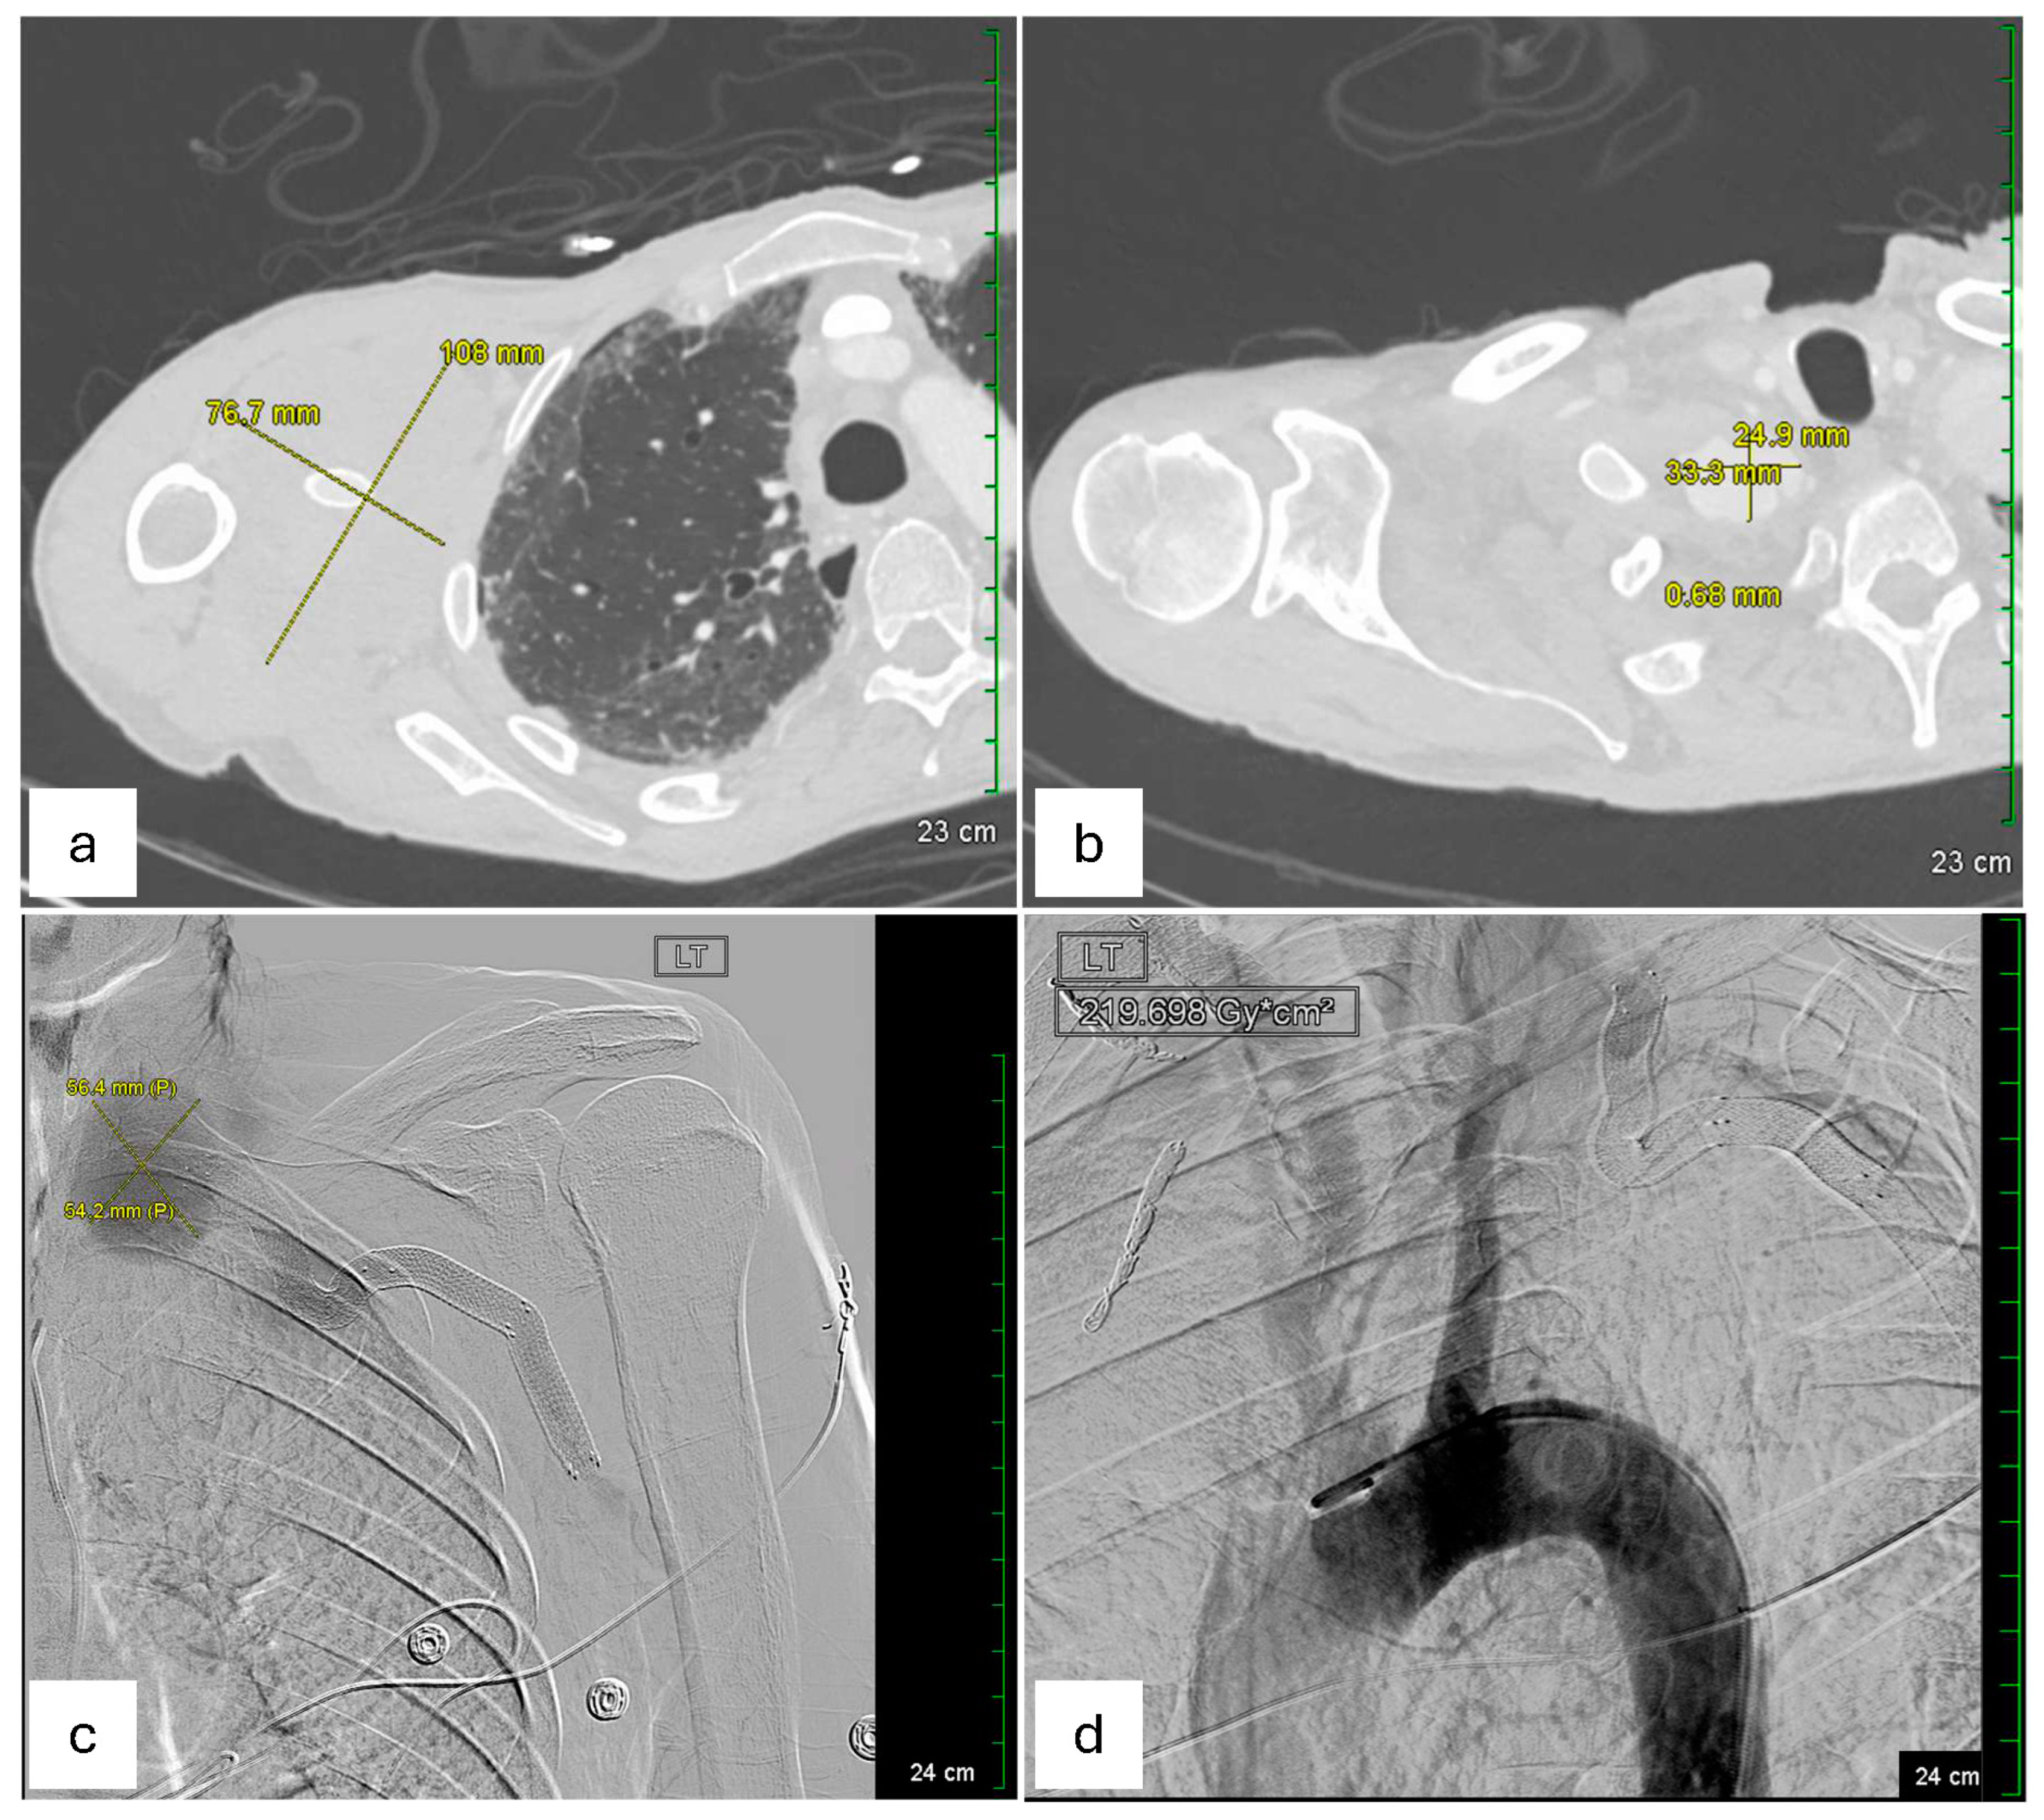

On hospital day 4 (3 days after endovascular repair of the left subclavian artery aneurysm), a repeat CT scan (Figure 3) was performed. Axial chest images (Figure 3a) showed a trace right pneumothorax (yellow arrow), unchanged since the day of admission. Sequential axial views (Figure 3b,c) demonstrated the right axillary hematoma, stable in size since hospital day 2 and without imaging findings suggestive of superinfection. Finally, an axial view of the proximal right subclavian artery (Figure 3d) revealed a type 1A endoleak in the right subclavian artery stent, indicating a possible proximal seal failure or ongoing infection that prevented full exclusion of the aneurysm (as pointed by the yellow arrow in Figure 3d). Although the patient’s white blood cell count gradually improved, and follow-up blood cultures eventually turned negative on hospital day 4 (as shown in Table 1), the possibility of a mycotic stent graft persisted. Vascular Surgery concluded that definitive source control might necessitate surgical graft explanation with extensive debridement, a high-risk procedure best conducted in a tertiary or quaternary center.

Figure 3. CTA on hospital day 4, 3 days after endovascular repair of the left subclavian artery aneurysm). (a) Axial chest CTA shows a trace right pneumothorax (yellow arrow), unchanged since the day of admission. (b,c) Sequential axial views demonstrating the right axillary hematoma, which remains stable in size since hospital day 2, without imaging findings suggestive of superinfection. (d) Axial view of the proximal right subclavian artery reveals residual but diminished aneurysmal filling around the stent graft (pointed by the yellow arrow), representing improvement compared with earlier imaging on the day of admission.